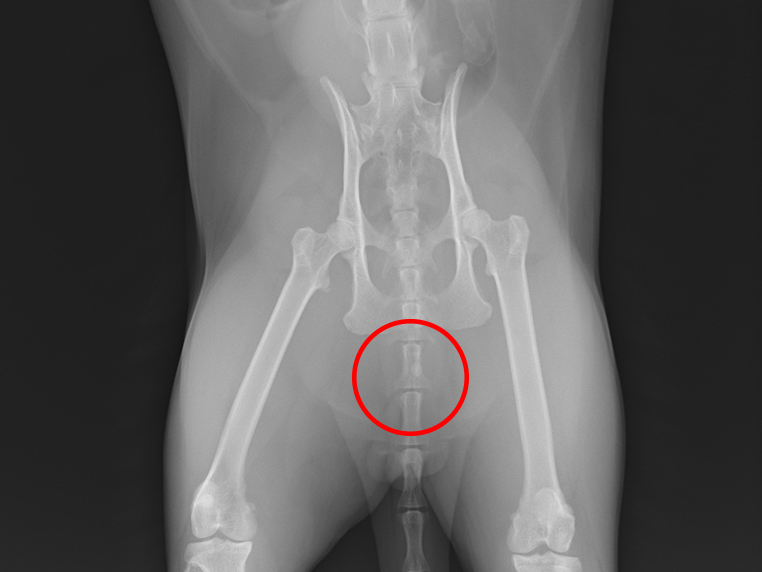

レントゲン検査を行ったところ、尿道の中にたくさんの結石が見つかりました。そこで、麻酔をかけて結石を膀胱の中に戻し、内視鏡を使った腹腔鏡手術で膀胱の結石を取り除く治療を行いました。

レントゲン画像にて尿道の結石の個数を確認